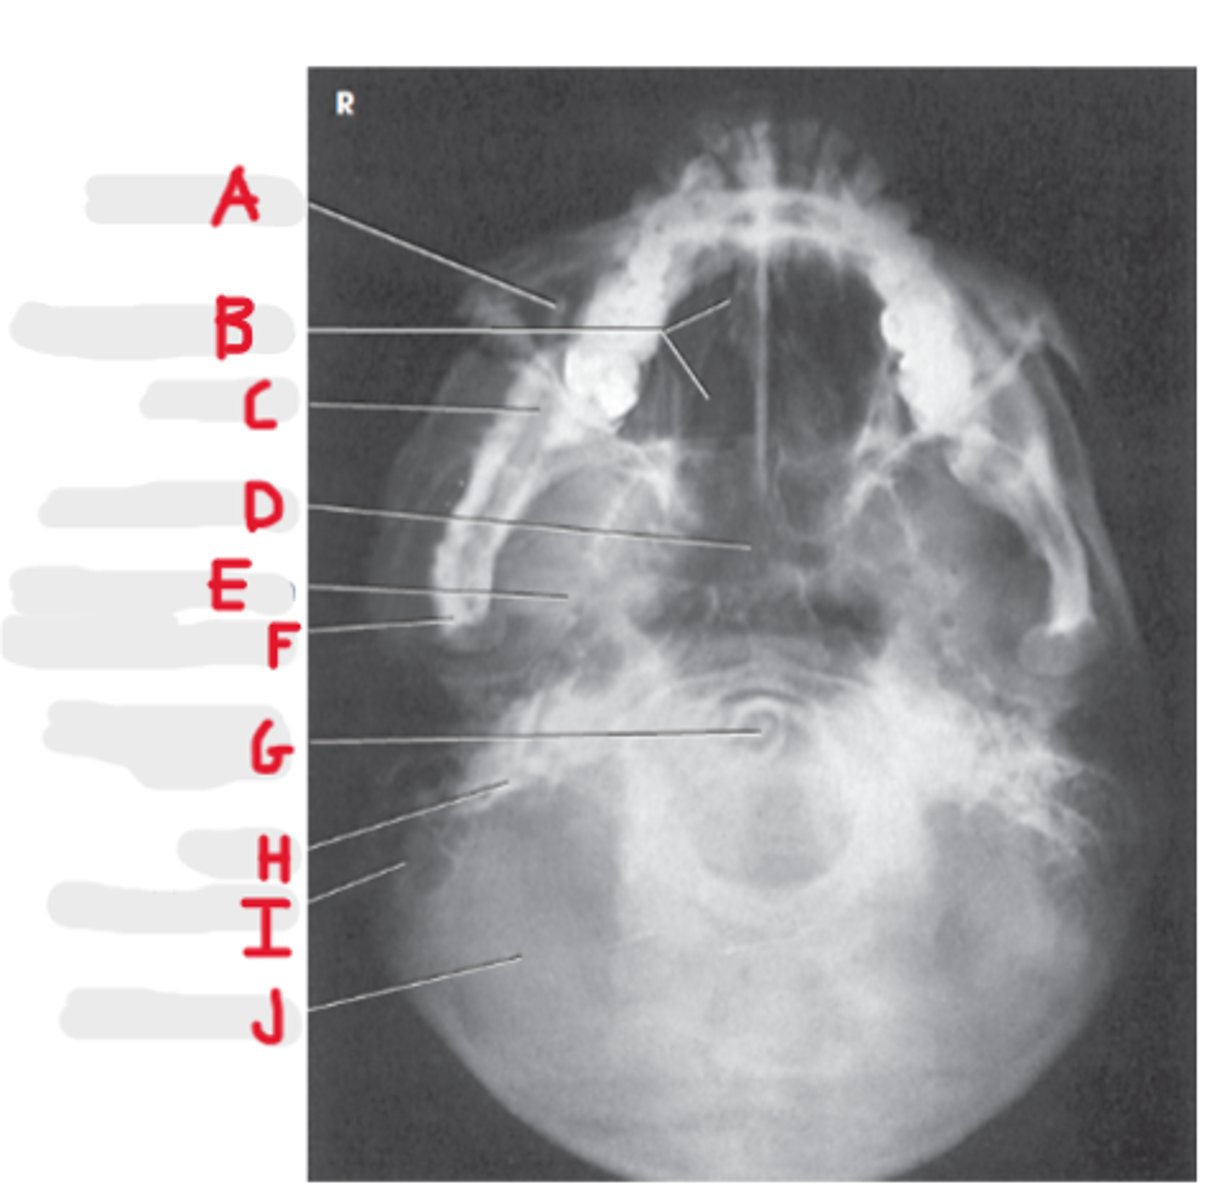

Coronal Suture

A

Orbital roof

B

Sella turcica

C

Sphenoid sinus

D

Petrous portion of temporal bone

E

Temporomandibular joint

F (jt)

EAM

G

Mandibular rami

H

Lateral Skull

What projection is this?

CR 2 inches superior to EAM

What is the CR for a lateral skull?

Interpupillary line (IPL)

What line is perpendicular to the IR for a lateral skull?

IOML and MSP

What line is parallel to the IR?

BOTH!

What lateral do we do for a skull?